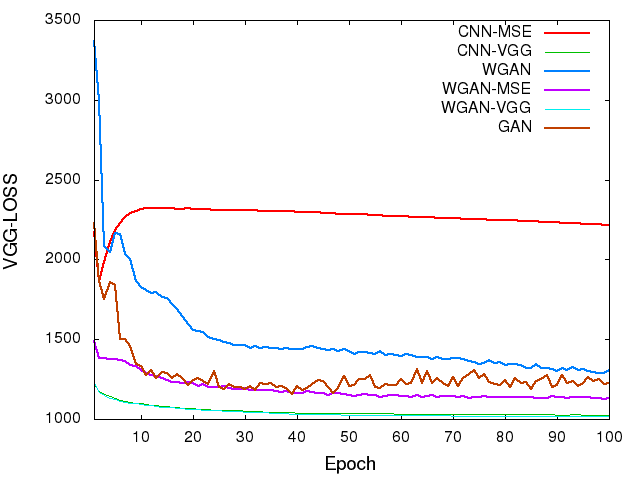

To visualize the convergence of the networks, we calculated the MSE loss and VGG loss over the 5,056 image patches for validation according to Eqs. (4) and (6) after each epoch. Fig. 4 shows the averaged MSE and VGG losses respectively versus the number of epochs for the five networks. Even though these two loss functions were not used at the same time for a given network, we still want to see how their values change during the training. In the two figures, both the MSE and VGG losses decreased initially, which indicates that the two metrics are positively correlated. However, the loss values of the networks in terms of MSE are increasing in the following order, CNN-MSEWGAN-MSEWGAN-VGGCNN-VGG (Fig. 4a), yet the VGG loss are in the opposite order (Fig. 4b). The MSE and VGG losses of GAN network are oscillating in the converging process. WGAN-VGG and CNN-VGG have very close VGG loss values, while their MSE losses are quite different. On the other hand, WGAN perturbed the convergence as measured by MSE but smoothly converged in terms of VGG loss. These observations suggest that the two metrics have different focuses when being used by the networks. The difference between MSE and VGG losses will be further revealed in the output images of the generators.

In order to show the convergence of WGAN part, we plotted the estimated Wasserstein values defined as in Eq. (3). It can be observed in Fig. 4(c) that increasing the number of epochs did reduce the W-distance, although the decay rate becomes smaller. For the WGAN-VGG curve, the introduction of VGG loss has helped to improve the perception/visibility at a cost of a compromised loss measure. For the WGAN and WGAN-MSE curves, we would like to note that what we computed is a surrogate for the W-distance which has not been normalized by the total number of pixels, and if we had done such a normalization the curves would have gone down closely to zero after 100 epochs.